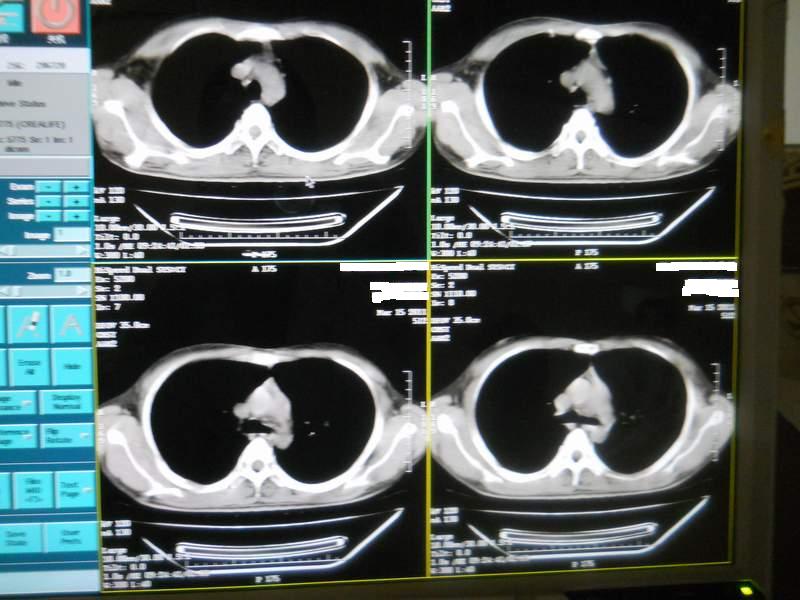

肺霉菌感染

男,22岁,一年前诊断马尔菲尼青霉菌感染,多次复查CT。多次HIV阴性。最近两次CT图片。有实验室结果。

最近实验室检查结果:霉菌感染。